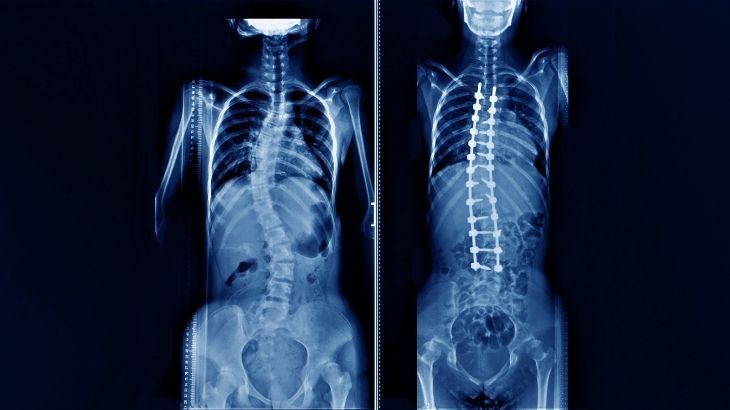

İdiopatik Skolyoz

İdiopatik skolyoz, omurganın yanlara doğru eğildiği en yaygın skolyoz türlerinden biridir. ve genellikle ergenlik döneminde ortaya çıkar. En sık görülen skolyoz türü olmasına rağmen, doğumsal, nöromüsküler veya travmatik skolyoz gibi bilinen hiçbir neden bu durumun gelişimini açıklamaz.